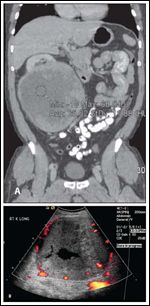

FIGURE 3

Images of the Original Right Kidney Tumor

DR. SUBY-LONG: Review of the initial outside CT revealed an 18-cm right renal mass with extensive heterogeneity and no demonstrable macroscopic fat. There were no liver lesions on the initial CT (Figure 3A). An ultrasound obtained within 10 days of the initial CT revealed an 18-cm solid, heterogeneous, moderately vascular mass with central necrosis (Figure 3B).